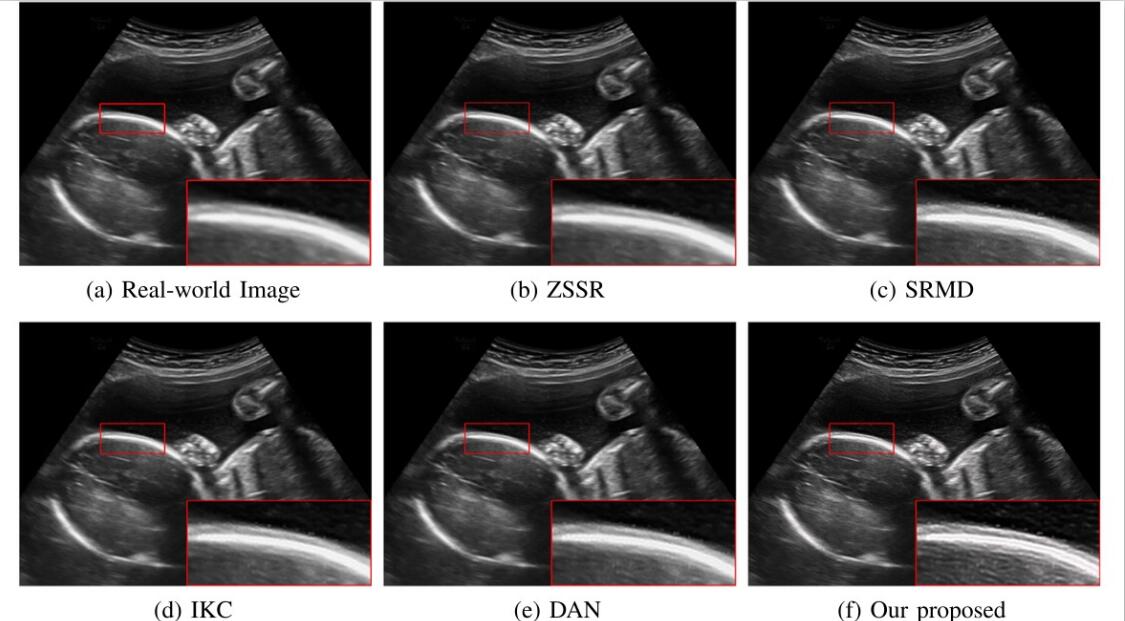

对于超声临床诊断而言,超声影像超分辨(ultrasound image super-resolution)可以提高超声成像质量,从而提高疾病诊断的准确性。但由于传感设备和传输介质的差异,实际场景中超声成像其退化模糊过程是未知且不可控的。为了解决未知退化场景超声医学影像准确超分辨的难题,团队提出了一种有效的基于退化模糊自估计且结合渐进残差学习和记忆提升机制的超声影像盲超分方法,初步实现了真实场景超声影像准确超分辨。相关研究成果发表在人工智能、计算机医学信息交叉领域一区TOP期刊《IEEE Journal of Biomedical and Health Informatics》(IF: 7.7)。beat365官网为论文第一完成单位,计算机学院刘恒教授、硕士生刘建勇分别为论文第一、第二作者。

(真实场景超声影像盲超分效果对比图)